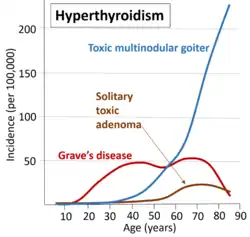

Graves' disease is the cause of about 50% to 80% of the cases of hyperthyroidism in the United States.[1][7] Other causes include multinodular goiter, toxic adenoma, inflammation of the thyroid, eating too much iodine, and too much synthetic thyroid hormone.[1][2] A less common cause is a pituitary adenoma.[1] The diagnosis may be suspected based on signs and symptoms and then confirmed with blood tests.[1] Typically blood tests show a low thyroid stimulating hormone (TSH) and raised T3 or T4.[1] Radioiodine uptake by the thyroid, thyroid scan, and measurement of antithyroid autoantibodies (thyroidal thyrotropin receptor antibodies are positive in Graves disease) may help determine the cause.[1]

- Graves' disease. An autoimmune disease (usually, the most common cause with 50–80% worldwide, although this varies substantially with location- i.e., 47% in Switzerland (Horst et al., 1987) to 90% in the USA (Hamburger et al. 1981)). Thought to be due to varying levels of iodine in the diet.[25] It is eight times more common in females than males and often occurs in young females, around 20 to 40 years of age.[26]

- Toxic thyroid adenoma (the most common cause in Switzerland, 53%, thought to be atypical due to a low level of dietary iodine in this country)[25]

- Toxic multinodular goiter

In the United States, hyperthyroidism affects about 1.2% of the population.[3] About half of these cases have obvious symptoms, while the other half do not.[2] It occurs between two and ten times more often in women.[1] The disease is more common in those over the age of 60 years.[1]